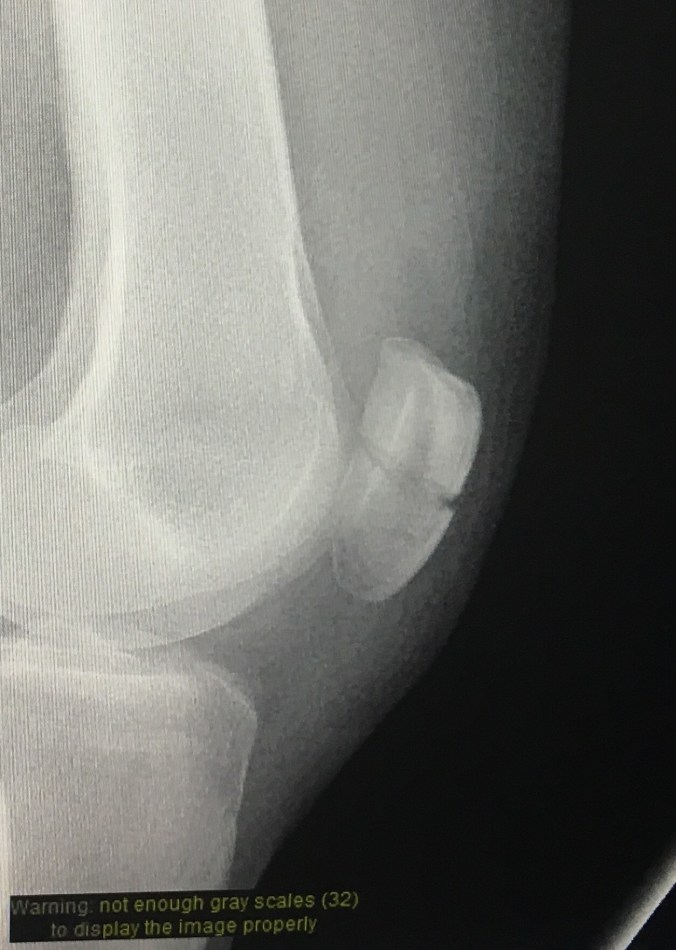

Upon painful reflection, I have three main problems: (1) despite a recent change in job I am no less of a freak who hides from life in her work than I was 3 weeks ago; (2) my patella is cracked completely in half; and (3) I should really shave my legs more often.